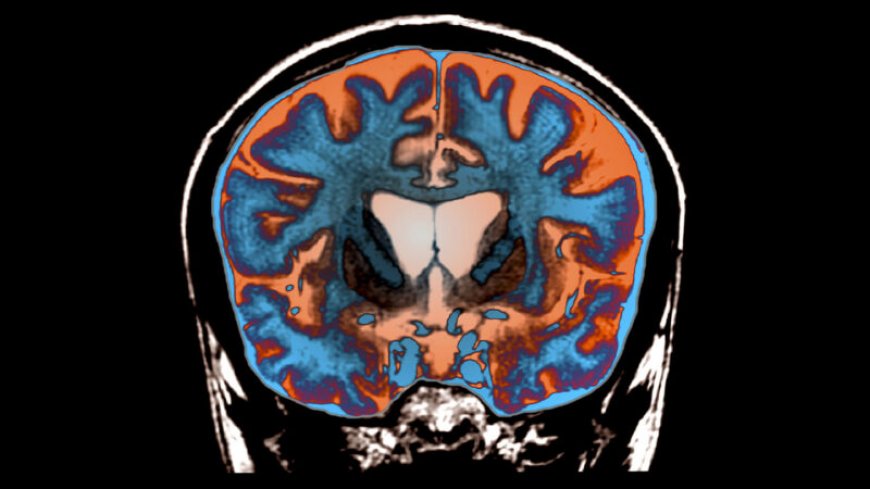

In the new research, Handsaker and colleagues examined individual brain cells in donated brains from people with and without the disease. After measuring the length of the repeated genetic bit in all the cells, the researchers found a “dramatic expansion” of the repeats in brain cells called striatal projection neurons, also known as medium spiny neurons, in people with Huntington’s, Handsaker said. The extra DNA wasn’t found in other types of brain cells in people with or without the disease.